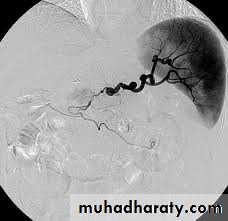

Splenic artery aneurysm

Aneurysms involving the splenic artery are estimated to occur at 0.04–1% of post-mortem examinations.They are twice as common in the female and are usually situated in the main arterial trunk. Although these are generally single, more than one aneurysm is found in a quarter of cases.

These may be a consequence of intra-abdominal sepsis and pancreatic necrosis in particular. They are more likely to be associated with arteriosclerosis in elderly patients.

The aneurysm is symptomless unless it ruptures and is more likely to be detected on a plain abdominal radiograph or ultrasound scan. It is unlikely to be palpable, although a bruit may be present.

Almost half the cases of rupture occur in patients younger than 45 years of age, and a quarter are in pregnant women, usually in the third trimester of pregnancy or at labour.

The treatment of choice previously consisted of splenectomy and removal of the diseased artery. Some surgeons advocate ligation of the proximal and distal ends of the sac to allow thrombosis of the aneurysm and partial or completelay.

Embolisation or endovascular stenting following selective splenic artery angiography can be considered

Splenic artery aneurism